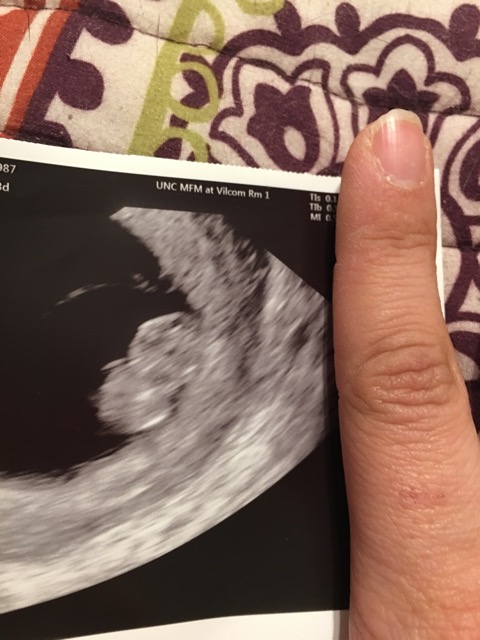

Ramzi Theory

Today I saw our little peanut and I’m in love. I’m thankful the little bean is measuring on time and has a heartbeat of 165. Any ideas on gender??